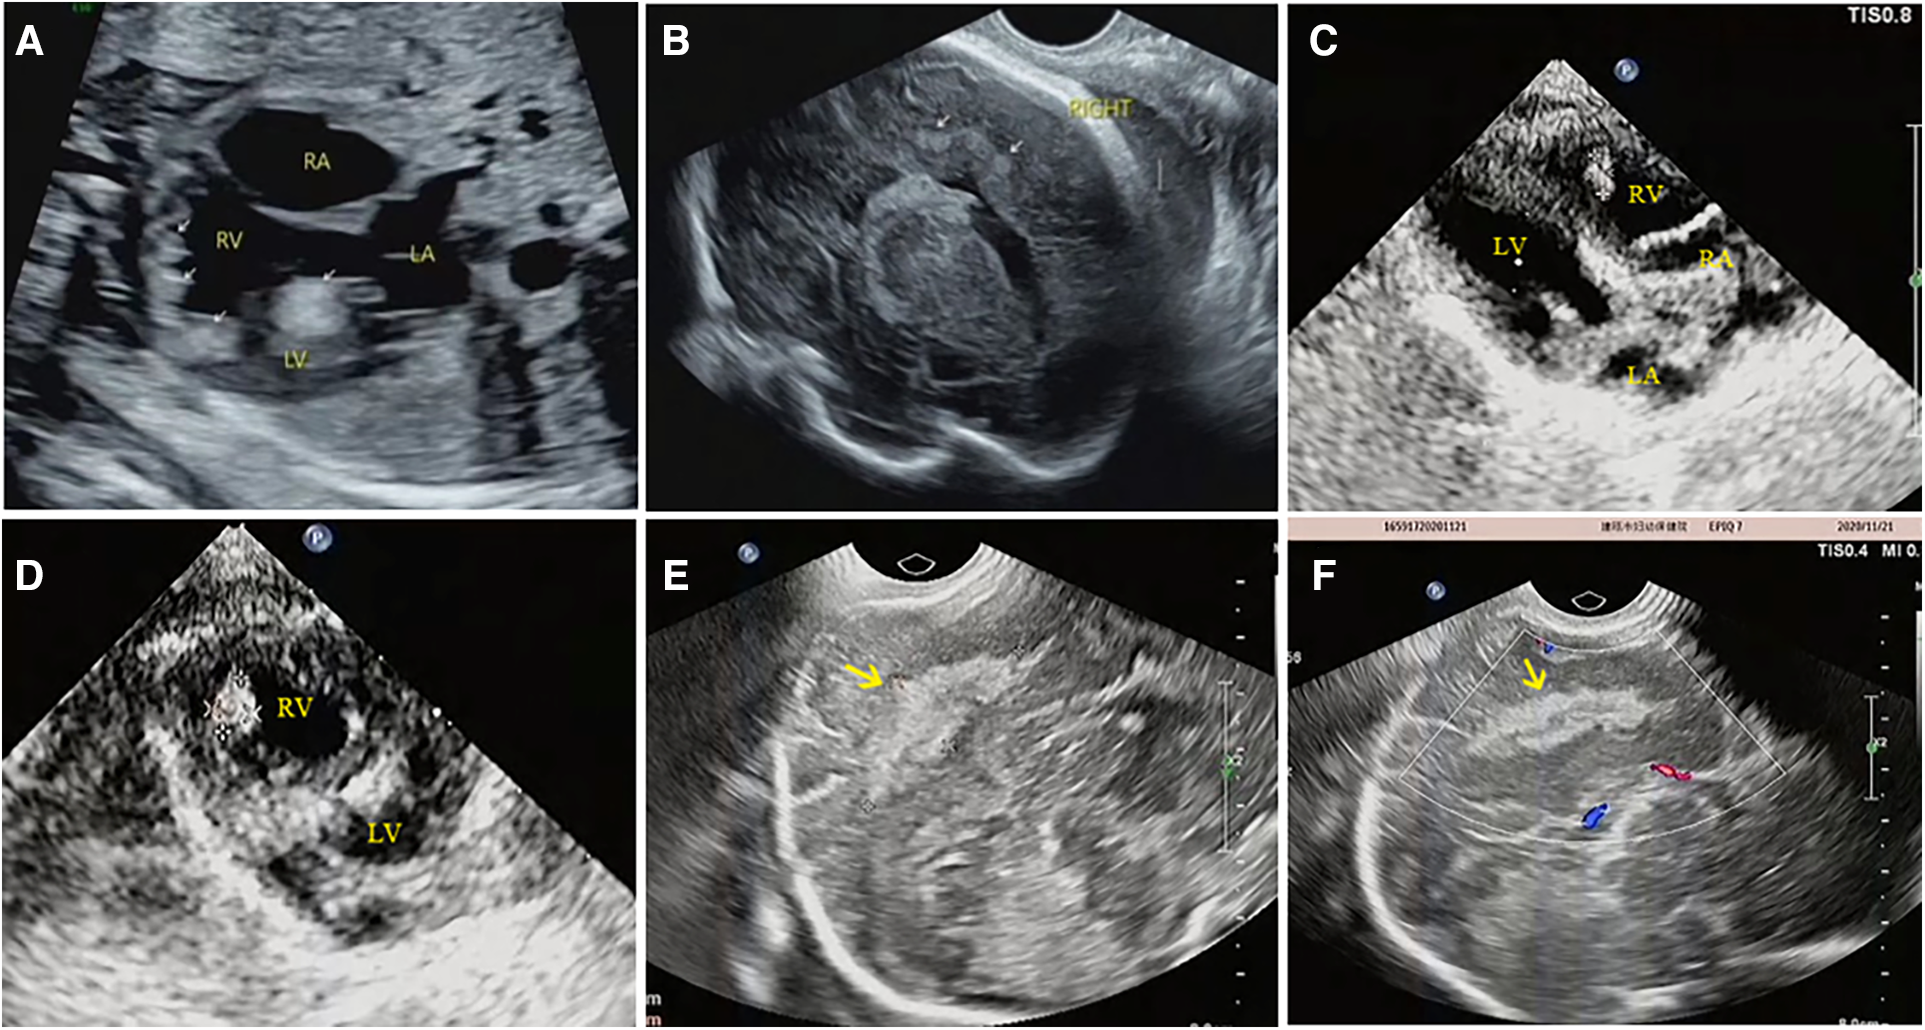

Figure 4

Prenatal and postnatal ultrasonography of cardiac rhabdomyoma complicated with cranial sclerotic nodules in case NO. 13. (A) Multiple slightly hyperechoic nodules in the ventricle of the fetal heart at 28 weeks of gestation. (B) Multiple hyperechoic intracranial nodules of the fetal heart at 28 weeks of gestation; however, no intracranial lesions were detected by MRI at the same time. (C,D) Multiple slightly hyperechoic nodules in the ventricle of the baby at 1 month after birth. (E,F) Hyperechoic intracranial nodule of this baby at the same time.

It is worth mentioning that our study found difference between ultrasound and MRI in detecting fetal intracranial lesions. Previous studies have suggested that subependymal nodules are more easily identified on fetal imaging, however, subcortical lesions are more commonly detected in postnatal brain MRI (10). Our analysis of imaging data found that prenatal ultrasound mostly identifies nodules in the brain parenchyma (90.9%), while prenatal brain MRI primarily detects subependymal nodules (93.3%). For example, ultrasound detected brain parenchyma nodules in case NO. 51, while brain MRI found subependymal nodules (Figure 2). In case NO. 13, prenatal ultrasound identified multiple intracranial nodules, whereas prenatal brain MRI didn't show any abnormalities. However, postpartum ultrasound and neonatal brain MRI revealed intracranial nodules (Figure 4). These phenomena suggested that ultrasound might detect specific fetal brain lesions not visible on MRI, warranting further investigation.